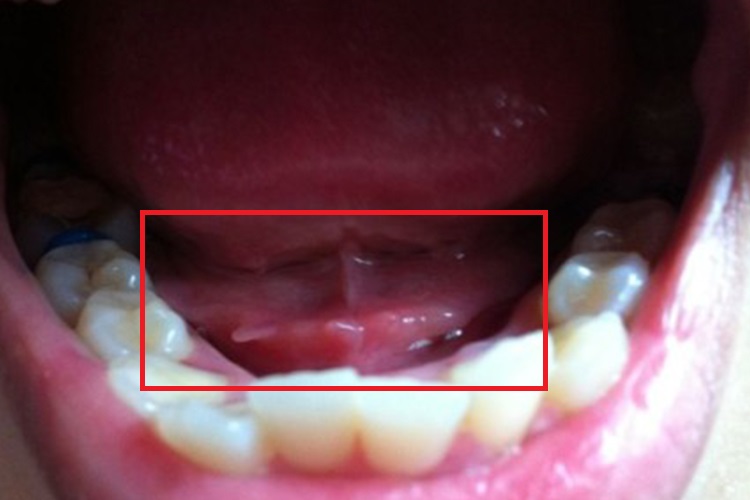

舌下肉芽:舌下肉芽表面常呈鲜红色,颗粒状组织增生,柔软湿润,似新鲜肉芽,触之易出血而无痛觉,多与局部长期反复的炎症刺激有关。

舌下尖锐湿疣:舌下尖锐湿疣表现为单个或多个小的结节,有蒂或无蒂,可逐渐增大或融合,形成菜花状、乳头状赘生物,颜色呈肉色或苍白色。